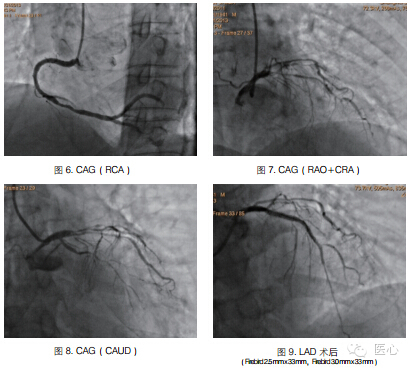

患者症状逐渐稳定,生命体征平稳,2天后拔除气管插管。请胸外科及肺内科会诊,建议先处理冠脉情况,待心脏病情稳定后行化疗,不考虑外科手术。与家属讨论后,经右桡动脉行冠脉造影提示LM(-),LAD弥漫性病变,中段次全闭塞,高位D1狭窄75%,LCX细小,弥漫性斑块,RCA远端斑块形成,右优势型。于LAD置入Firebird 2.5 mm x 33 mm、Firebird 3.0 mm x 33 mm支架2枚,手术顺利(图6~9)。术后给予正规药物治疗。3天后出院,建议肺内科进一步治疗。